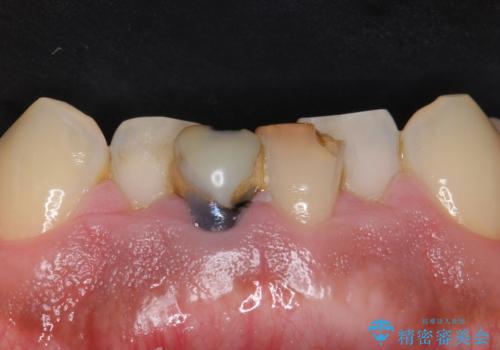

- 左下奥歯の銀歯を白くしたいと来院された方の症例です。

銀歯を除去後、セラミックインレーによる修復を行いました。